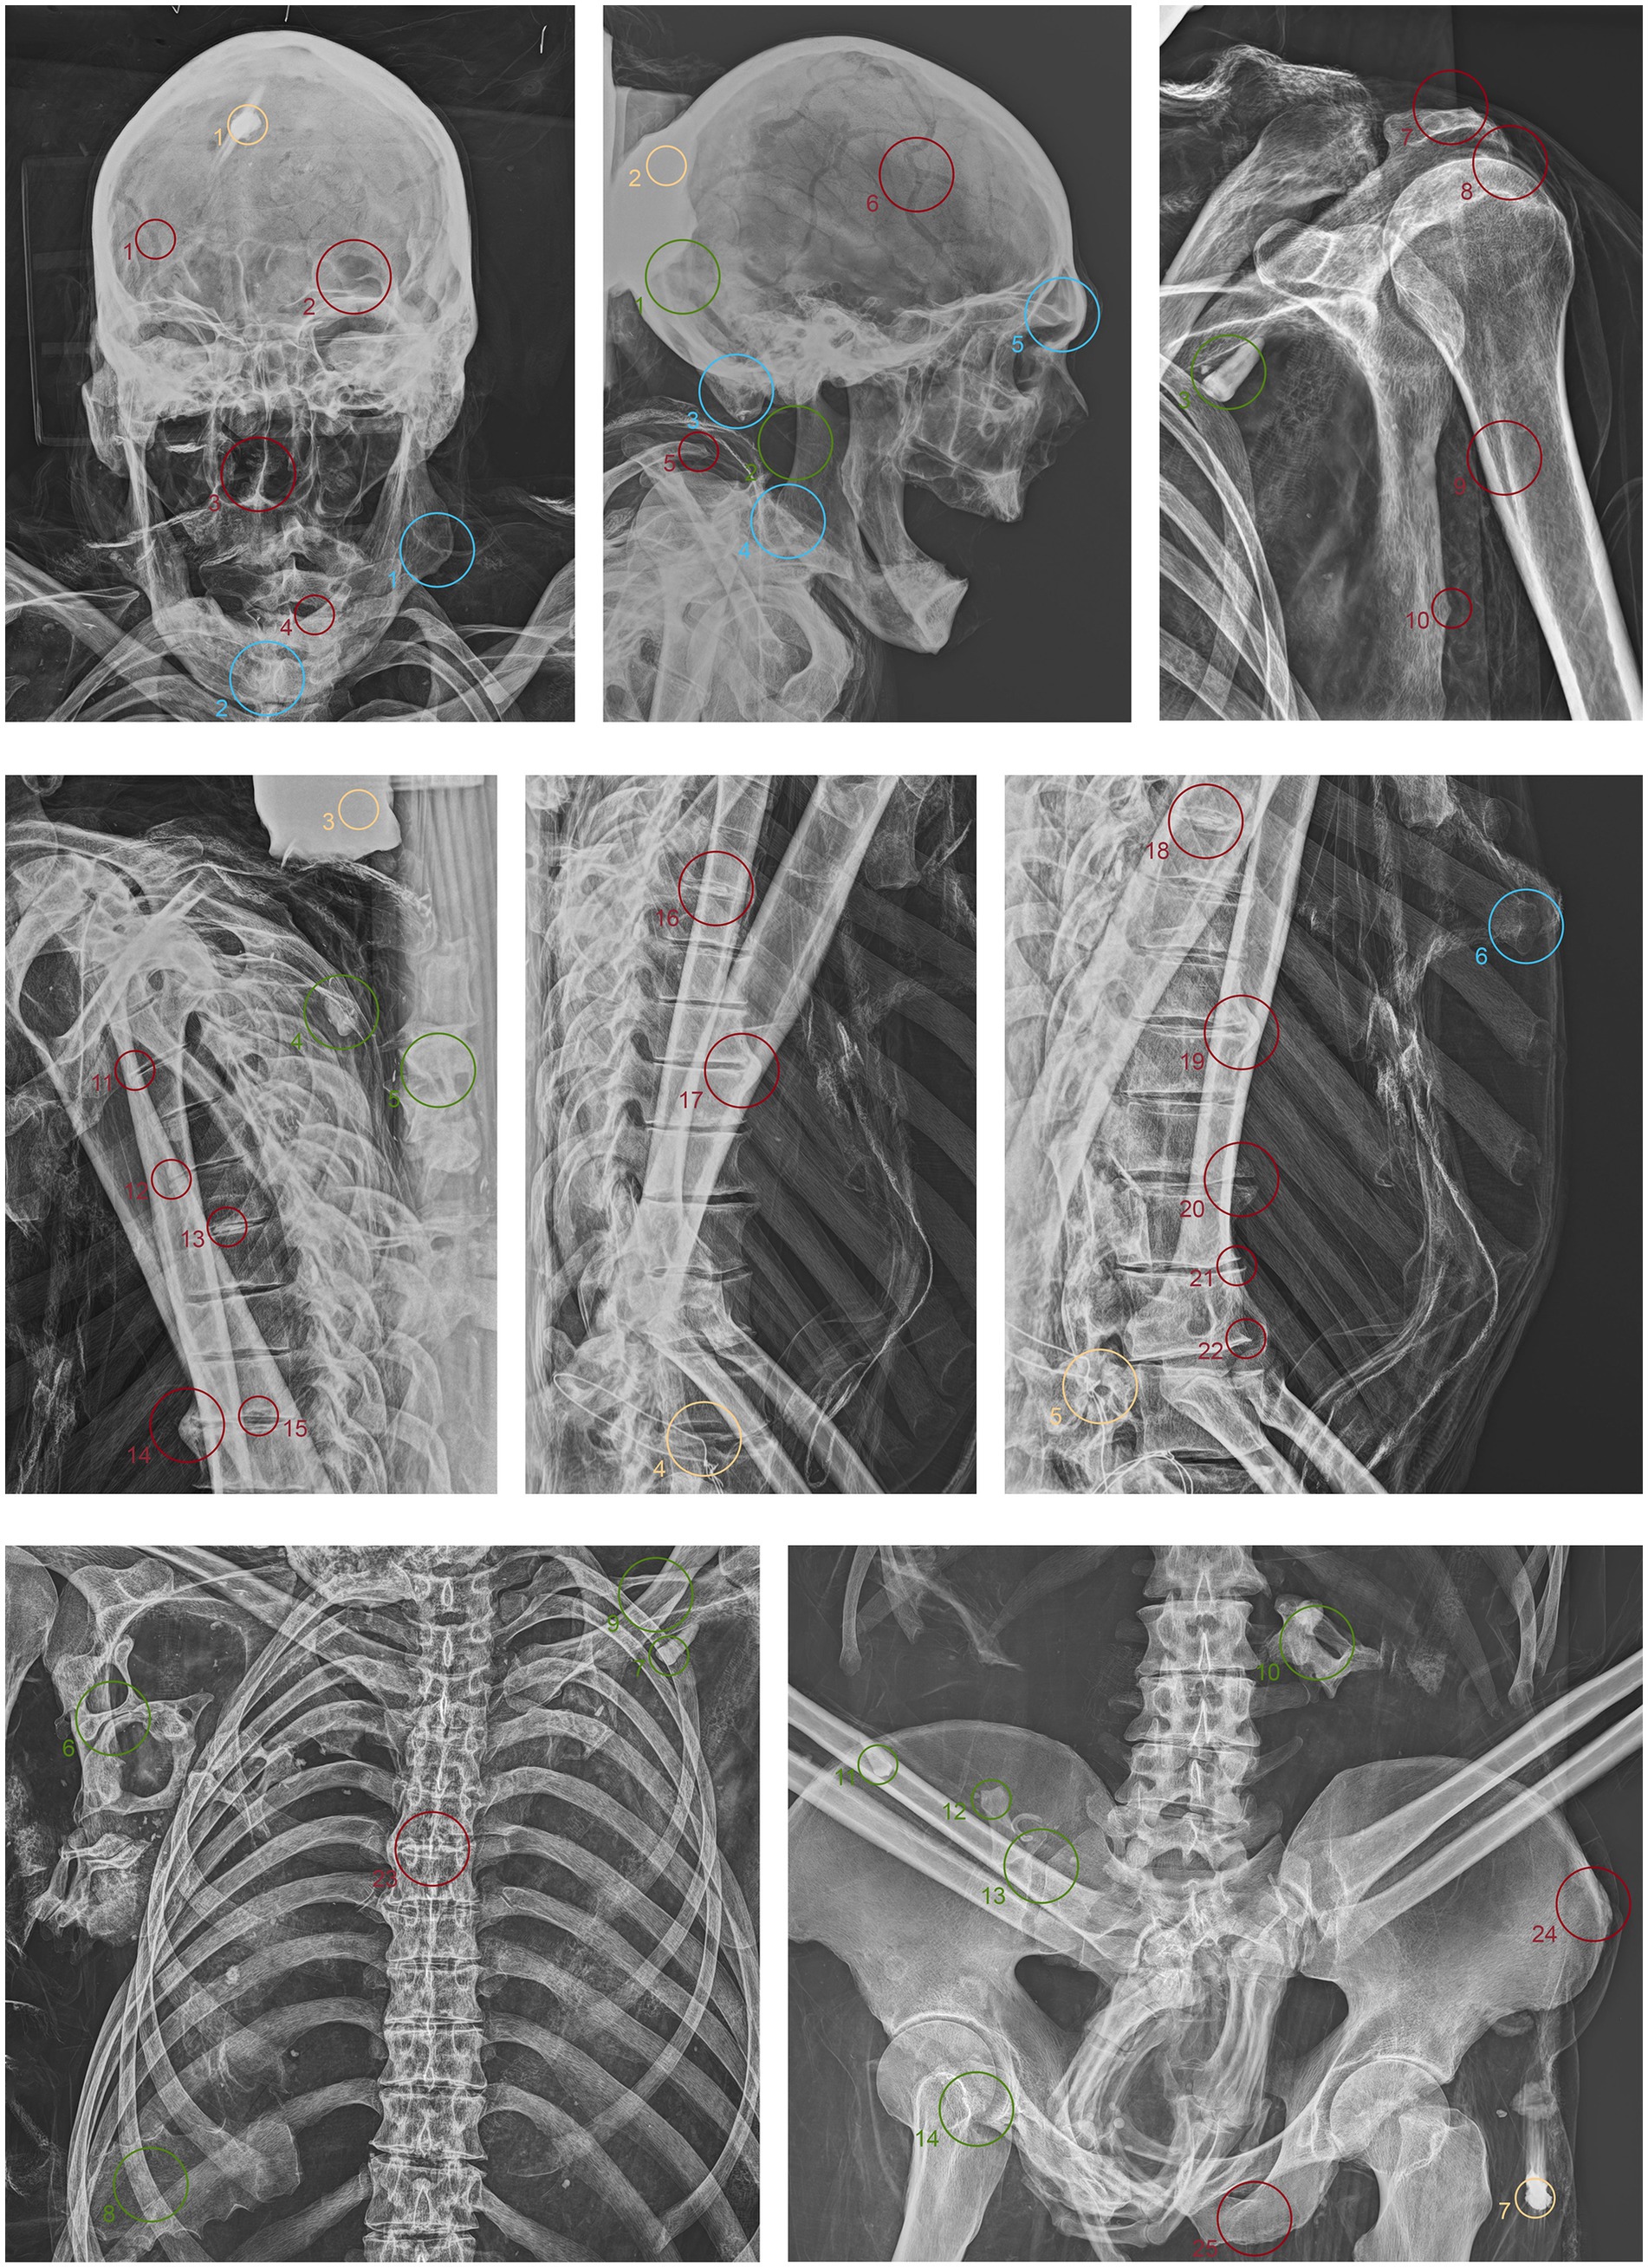

3.1 Textile analyses

ID1. The liturgical vestments of ID1 consist of a chasuble, a stole, an alb, and a pillow cover. Artisans crafted the chasuble’s passementerie with two distinct threads: an oxidized metallic thread and a silk thread (Figure 3a.1,2). X-ray analysis revealed the intricate weaving pattern running along the entire perimeter of the chasuble (Figure 3a.2). The distinctive feature identified was the use of metallic foil as the weft; the warp, presumably organic, was not detected (Figure 3a.1). The density of the weave and the loss of metallic foil due to significant oxidation were observed, with small fragments identified as fibrils. Fabric folds caused irregularities in the X-ray images. The passementerie on the maniple was likely woven on a loom, with a metallic thread warp (possibly with a silk core) and an undetermined weft (Figure 3a.3). The passementerie on the pillow cover exhibited a different weaving technique compared to the chasuble. A metallic foil, twisted around what appears to be a silk thread core, runs through both the warp and weft. Irregularities in the X-ray images were again due to fabric folds (Figure 3b.1).

Figure 3. (a) Anteroposterior radiograph of the skull of ID1; (b) Anteroposterior radiograph of the lower limbs of ID1; (c) Anteroposterior radiograph of the thorax of ID2; (d) Anteroposterior radiograph of the right femur of ID2; (e) Anteroposterior radiograph of the thorax of ID3; (f) Lateral radiograph of the lower limbs of ID3. The three-dimensional reconstructions, separated by a dashed line from the radiographic acquisitions, correspond to the radiographed anatomical areas and are numbered accordingly.

ID2. The liturgical vestments of ID2 consist of a chasuble, a stole, a pillow cover, and what might be a maniple. The passementerie on the chasuble and stole was made with bobbin lace using two threads: an oxidized metallic foil and a silk thread. X-ray analysis revealed the metallic foil twisted around an organic thread core, present in both the warp and the weft (Figure 3c.1). The weave was more complex than that of the first exhibit, with a decorative pattern of alternating rhombuses and small lozenges. The radiographic analysis highlighted the intricate technique, which is difficult to discern with the naked eye due to significant oxidation of the metallic thread (Figure 3d.1).

ID3. The liturgical vestments of ID3 consist of a chasuble, a stole, a maniple, an alb, and footwear. A loom set to create a herringbone pattern wove two threads into the passementerie adorning the chasuble stole and maniple (Figure 3e.1,2): a partially oxidized gold metallic foil and a silk thread. Additionally, there was bobbin lace with a gold foil twisted around a silk core, featuring a net motif with undulating terminations (partially oxidized). X-ray analysis detected two different weaving techniques. The first, visible only in the weft direction, is a metallic foil twisted around an organic thread. The galloon, primarily made of organic material, did not reveal the weaving pattern through radiographic analysis. The second type of passementerie, clearly visible, showed a net motif entirely composed of twisted metallic foil (Figure 3f.1,2).

3.2 Taphonomic analyses

ID1. In the neurocranium, fine material occupies the base, partially filling the occipital region in a layer parallel to the deposition plane (Figure 4.1,5 green). The left frontozygomatic suture is notably more pronounced than the contralateral side due to a slight clockwise rotation of the frontal bone away from the zygomatic bone (Figure 4.2 green). The mandible is also displaced from its anatomical position, with a counterclockwise rotation, pivoting on the mandibular condyle and resulting in the dislocation of the contralateral side (Figure 4.3,6 green). All teeth are absent except for the left upper second premolar (Figure 4.7 green). Other teeth are visible on the floor of the nasopharynx and within the thoracic cavity, to the left of the tenth and eleventh thoracic vertebrae (Figure 4.4,8–10 green). The proximal phalanx of the right thumb is not in anatomical position (Figure 4.11 green), and both distal epiphyses of the fibulae are lacking (Figure 4.12,13 green).

Figure 4. Anteroposterior and lateral radiographic acquisitions of the individual ID1. Green highlights indicate areas of interest for taphonomic study, yellow highlights indicate areas relevant to the assessment of restorations predating this study, violet is used for entomological analysis, blue for anthropological aspects, and red for paleopathological evidence.

ID2. In this subject, fine material is detectable in the occipital region, forming a single layer parallel to the mummy’s deposition axis (Figure 5.1 green). The cervical vertebrae and the first thoracic vertebra are no longer in anatomical connection, disrupting the continuity of the spinal column (Figure 5.2 green). They have migrated beneath the right side of the thorax at the mid-thoracic level, extending down to the lumbar region (Figure 5.5,6,10 green). Additionally, some teeth are not in an anatomical position—one within the thoracic cavity and another in the pelvic area (Figure 5.3,4,7,11 green). The sternum has migrated to the lower right thoracic area, and a medial phalanx is also displaced (Figure 5.8,12 green). The left clavicle is more vertical compared to the contralateral side, and, in addition, there is a slight retraction of the arm and forearm (Figure 5.9 green). The sacroiliac articular surface is particularly prominent, as is the pubic symphysis, exposed due to the separation of the two halves (Figure 5.13; Figure 6.1 green). The right femur is also rotated laterally by about 90° (Figure 5.14 green), causing lateral rotation of the knee and tibia. Notably, a fold in the soft tissues of the left thigh is evident at the level of the distal diaphysis of the left femur (Figure 6.2–4 green).

Figure 5. Anteroposterior and lateral radiographic acquisitions of the pelvis and upper limb of the individual ID2. Green highlights indicate areas of interest for taphonomic study, yellow highlights indicate areas relevant to the assessment of restorations predating this study, violet is used for entomological analysis, blue for anthropological aspects, and red for paleopathological evidence.

Figure 6. Anteroposterior and lateral radiographic acquisitions of the pelvis and lower limb of individual ID2. Green highlights indicate areas of interest for taphonomic study, yellow highlights indicate areas relevant to the assessment of restorations predating this study, violet is used for entomological analysis, blue for anthropological aspects, and red for paleopathological evidence.

ID3. As in the previous subjects, fine material is observed within the occipital region of the neurocranium (Figure 7.1 green). The hyoid bone is visible in its anatomical position (Figure 7.2 green). The upper spine remains in perfect anatomical alignment. However, there is a discontinuity between the first and second thoracic vertebrae, with the upper segment displaced anteriorly by approximately 4 cm in the sagittal plane (Figure 7.3,4 green). A bone fragment and the distal portion of the right fibula are recognized as fragmented at the level of the mid-diaphysis of the right femur (Figure 7.5,6 green).

Figure 7. Anteroposterior and lateral radiographic acquisitions of the individual ID3. Green highlights indicate areas of interest for taphonomic study, yellow highlights indicate areas relevant to the assessment of restorations predating this study, violet is used for entomological analysis, blue for anthropological aspects, and red for paleopathological evidence.

3.3 Artifact analyses

ID1. The metal nails within the wooden support boards for the mummy are visible (Figure 4.1,9,13,14 yellow). Metal wire appears on various sections of the body; on the mandible, the wire appears unfastened, and numerous fragments of similar wire are visible at the shoulder level (Figure 4.2–8 yellow). Several loops of metal wire connect the left humerus, ulna, and radius, loosely knotted at the elbow (Figure 4.10–12 yellow).

ID2. Similarly, the metal nails used to assemble the wooden bases housing the bodies are visible (Figure 5.1,7; Figure 6.1,4 yellow). A particularly radiodense rectangular element wraps around the occipital bone beneath the skull (Figure 5.2,3 yellow). As in the previously discussed subject, metal wire was used to wrap around the left elbow (Figure 5.4,5 yellow) and to bind and tighten the mummified tissues of the right leg (Figure 6.2,3 yellow).

ID3. In this individual, numerous nail used for the mummy supports are visible (Figure 7.1,6,8,11 yellow). In this case, one image highlights the more radiodense halo that characterizes many of the metallic elements of the supports (Figure 7.10 yellow). Several small pins with heads are positioned in the upper part of the subject (Figure 7.2,3,5 yellow), while iron wire binds the right wrist and hand, with loops extending to bind individual fingers (Figure 7.7,9 yellow).

3.4 Entomological analyses

The search for entomological evidence from the X-rays carried out on the three bodies revealed only a few interesting elements, in contrast to the data obtained from the hand collection of insects and their fragments from the bodies (data not published). In particular, a pair of barrel-like elements of a size (<1 cm) compatible with puparia are visible on ID1 at the pelvis cavity (Figure 4.1,2 violet). The elements are radio-dense and can be interpreted as whole puparia, with the dead immature insects inside or with rat/mouse excrements. In addition, two amphora-like elements are detectable on the leg of ID2 (Figure 6.1,2 violet). These elements are comparable with black mud-dauber wasps’ nests, however, due to their position no direct observations were carried out. So, this remains a potential hypothesis.

3.5 Anthropological analyses

ID1. In the lateral view, the pronounced glabella, well-defined nuchal crest, and the right angle formed by the mandibular ramus and body are evident (Figure 4.1–3 blue). The lambda suture appears completely open (Figure 4.4 blue). The sternocostal surfaces of the ribs are well-defined and free from deformities, erosions, or marginal sclerosis (Figure 4.5 blue). The sciatic notch is narrow, and the subpubic angle is less than 90° (Figure 4.6 blue). The cortical thickness of both femoral diaphyses suggests robust bone trophism (Figure 4.7 blue).

ID2. In the anteroposterior view, a big gonial eversion and a robust mental symphysis are evident, with a prominent mental protuberance and pronounced mental tubercles (Figure 5.1,2 blue). In the lateral view, the pronounced glabella, robust mastoid processes, and relatively open mandibular angle are visible (Figure 5.3–5 blue). The sternocostal surfaces of the ribs show deformities, erosions, and marginal sclerosis (Figure 5.6 blue). Both the lateral and anteroposterior views reveal a narrow sciatic notch (Figure 6.1 blue).

ID3. In both anteroposterior and lateral views, the sagittal suture and lambda are unfused (Figure 7.1,2 blue). The subject has a prominent gonion of the mandible, a mandibular angle near 90°, and a very pronounced glabella (Figure 7.3,4 blue). The presence of the right lower third molar is also evident, while the other three third molars are absent (Figure 7.5 blue). While the bones have fused, the manubrium and first sternebra remain separate, and fusion lines on the proximal ends of the fibulae and tibiae are still evident (Figure 7.6, 8–10 blue). The pelvis is robust, with a subpubic angle of approximately 90°, although the left hemipelvis is slightly rotated counterclockwise (Figure 7.7 blue).

3.6 Paleopathological analyses

ID1. X-ray lateral projection analysis of the skull reveals areas of reduced radiodensity that follow the course of the middle meningeal artery, suggesting the presence of a deep groove corresponding to the vessel’s anatomy (Figure 4.1 red). ID1. The X-ray lateral projection of the skull shows areas of reduced radiodensity along the path of the middle meningeal artery, indicating a pronounced groove that aligns with the artery’s course (Figure 4.1 red). In the lower thoracic spine, there are calcifications of the intervertebral space between the 8th and 11th vertebrae, more expressed toward the lumbar region and particularly evident in the lateral projection (Figure 4.2,3,5,6 red). This condition is not associated with marginal lipping on the edges of the vertebral bodies, nor are there any signs of osteolytic activity on the superior or inferior surfaces of the vertebrae (Figure 4.4 red). Calcifications are also visible starting from the articular sternal surface of ribs (Figure 4.7 red). Heterotopic ossification is observed in the pelvic area, corresponding to the sacroiliac joint surface. The anteroposterior projection of this anatomical region reveals osteophytes along the inferior margins of the joint in the ventral view (Figure 4.8,9 red). The non-closure of the sacral laminae up to S3 is also documented (Figure 4.19 red). The densification of bone tissue is observed in the distal diaphysis of both tibiae, approximately 1.7 cm from the distal articular surface (Figure 4.11,12 red).

ID2. The skull shows a dense network of venous impressions on the parietal bones, particularly visible in the anteroposterior projection (Figure 5.1,6 red), along with the presence of several Pacchioni’s foramina. The frontal sinuses expand laterally, almost reaching above the orbits (Figure 5.2 red). The anterior nasal spine appears slightly rotated to the right relative to its anatomical axis (Figure 5.3 red). This individual exhibit complete edentulism, associated with mature alveolar bone retracted from the alveolar region (Figure 5.4 red). Proceeding to the analysis of the appendicular skeleton, the acromion of the left clavicle shows marked roughness at the insertion area of the trapezius muscle, as at the origin of the subscapularis muscle (Figure 5.7 red). The joints between the humerus and scapula exhibit greater radiodensity (Figure 5.8 red). An area free of bone overlap allows the observation of increased radiodensity at the insertion of the pectoralis major muscle and inside the humerus-scapular joint (Figure 5.9 red). Heterotopic ossification is also noted on the margin of the lateral border of the scapula (Figure 5.10 red). The thoracic spine presents intervertebral calcification between the 5th and 6th vertebrae (Figure 5.13,16,18,23 red), fusion of the 8th and 9th vertebrae through a dense bony bridge (Figure 5.14,17,19 red), and intense osteophytic change along the margin of the entire segment, particularly evident between the 9th and 11th thoracic vertebrae (Figure 5.11,12,20–22 red). Sclerosis is observed in the superior and inferior vertebral articular surfaces, accompanied by granular and concave areas in the vertebral bodies (Figure 5.15 red). Osteophytes are observed at the insertion points of the oblique muscles on the iliac crest, at the various muscles originating from the ischial tuberosity, and at the insertion area of the iliopsoas muscle during the analysis of the pelvic girdle (Figure 5.24,25; Figure 6.1,2 red). The origin of the gastrocnemius muscle is also particularly pronounced (Figure 6.3 red). At the level of the knee joint, we noticed osteophytes on the margin of the right patella (Figure 6.4,5 red), both on the superior and inferior portions of the joint, as well as on the lateral articular margin of the distal femur and proximal tibia, with productive changes that have significantly altered the morphology of the joint (Figure 6.6,7 red). It is worth mentioning that osteophytes are also present at the insertion of the Achilles’ tendon (Figure 6.8 red).

ID3. The lateral projection of the skull highlights the morphology of the pulp chamber of the left second lower molar, which exhibits a “chair-shaped” configuration (Figure 7.1 red). The 8th thoracic vertebra is compressed in the anterior view, accompanied by a milder compression of the 7th vertebra. This condition is associated with osteophytes along the margins of both vertebral bodies, as well as the preceding and following vertebrae (Figure 7.2,3 red). Additionally, the vertebral endplates, which are slightly sclerotic, show small areas of erosion in the central portion (Figure 7.4,5 red). In this individual, the insertions of the oblique muscles on the iliac crest also show significant alterations in this region (Figure 7.6 red).